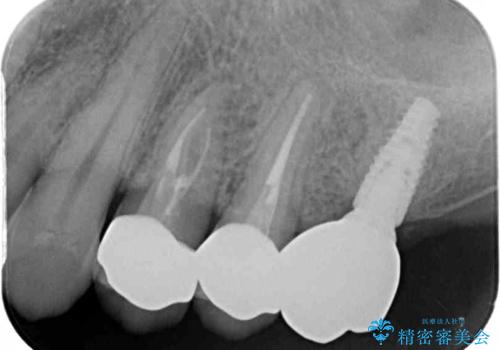

根管治療を行った歯には特に症状がないため、速やかにオールセラミッククラウンにて補綴治療を行うこととしました。

補綴治療前は食後はいつもものが挟まっていたそうですが、補綴治療後はものが挟まる悩みから解放されたとのことでした。